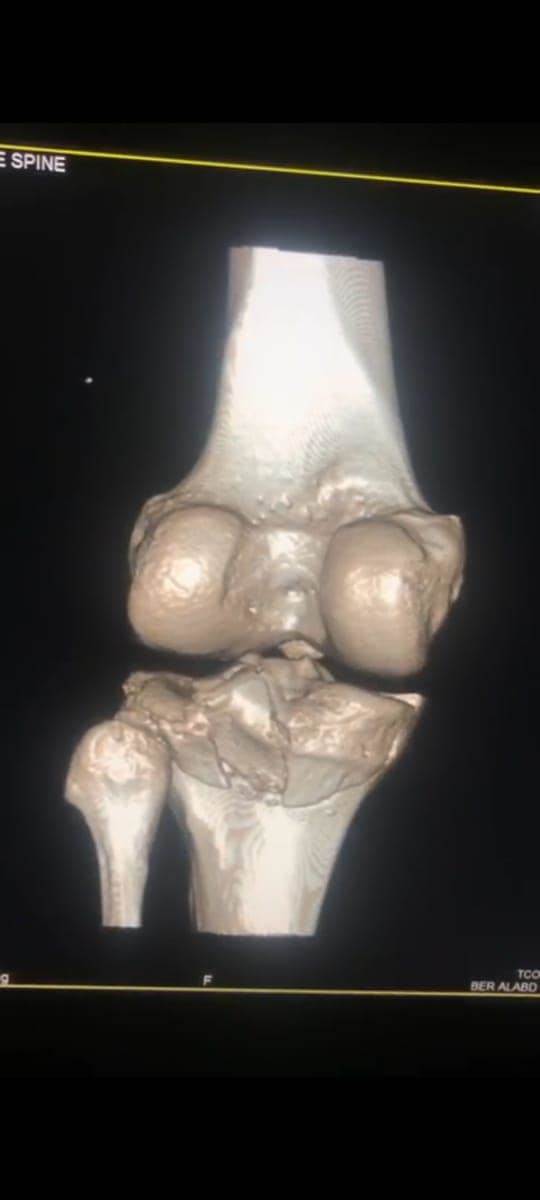

مشيرًا الى أن ذلك النوع من الكسور يكون قريبًا جدًا من الأعصاب والأوعية الدموية الرئيسية للساق والتي توجد خلف مفصل الركبة.. حيث تم الوصول الى الكسر وإعادة بناء سطح المفصل وتثبيته باستخدام شريحة ومسامير وأسلاك معدنية باستخدام جرح ٧ سنتيمترات خلف الركبة واستخدام مسامير جانبية مجوفة بدون فتح لتثبيت الجزء الخارجى من سطح المفصل، وتم الاطمئنان على الأوعية الدموية قبل إفاقة المريض، وبعد تمام الإفاقة.. تم الاطمئنان على الأعصاب والأوعية للمريض.

وأضاف أنه نظرًا لقرب هذا الكسر من سطح المفصل تم عمل أشعة مقطعية بعد الجراحة للتأكد من جودة بناء المفصل وعدم وجود أى بروز للمسامير داخل المفصل، وجارٍ تحضير المريض لعمل رنين مغناطيسى لتحديد الأربطة الداخلية والخارجية للركبة التي ستحتاج لإعادة بناء بالمنظار.